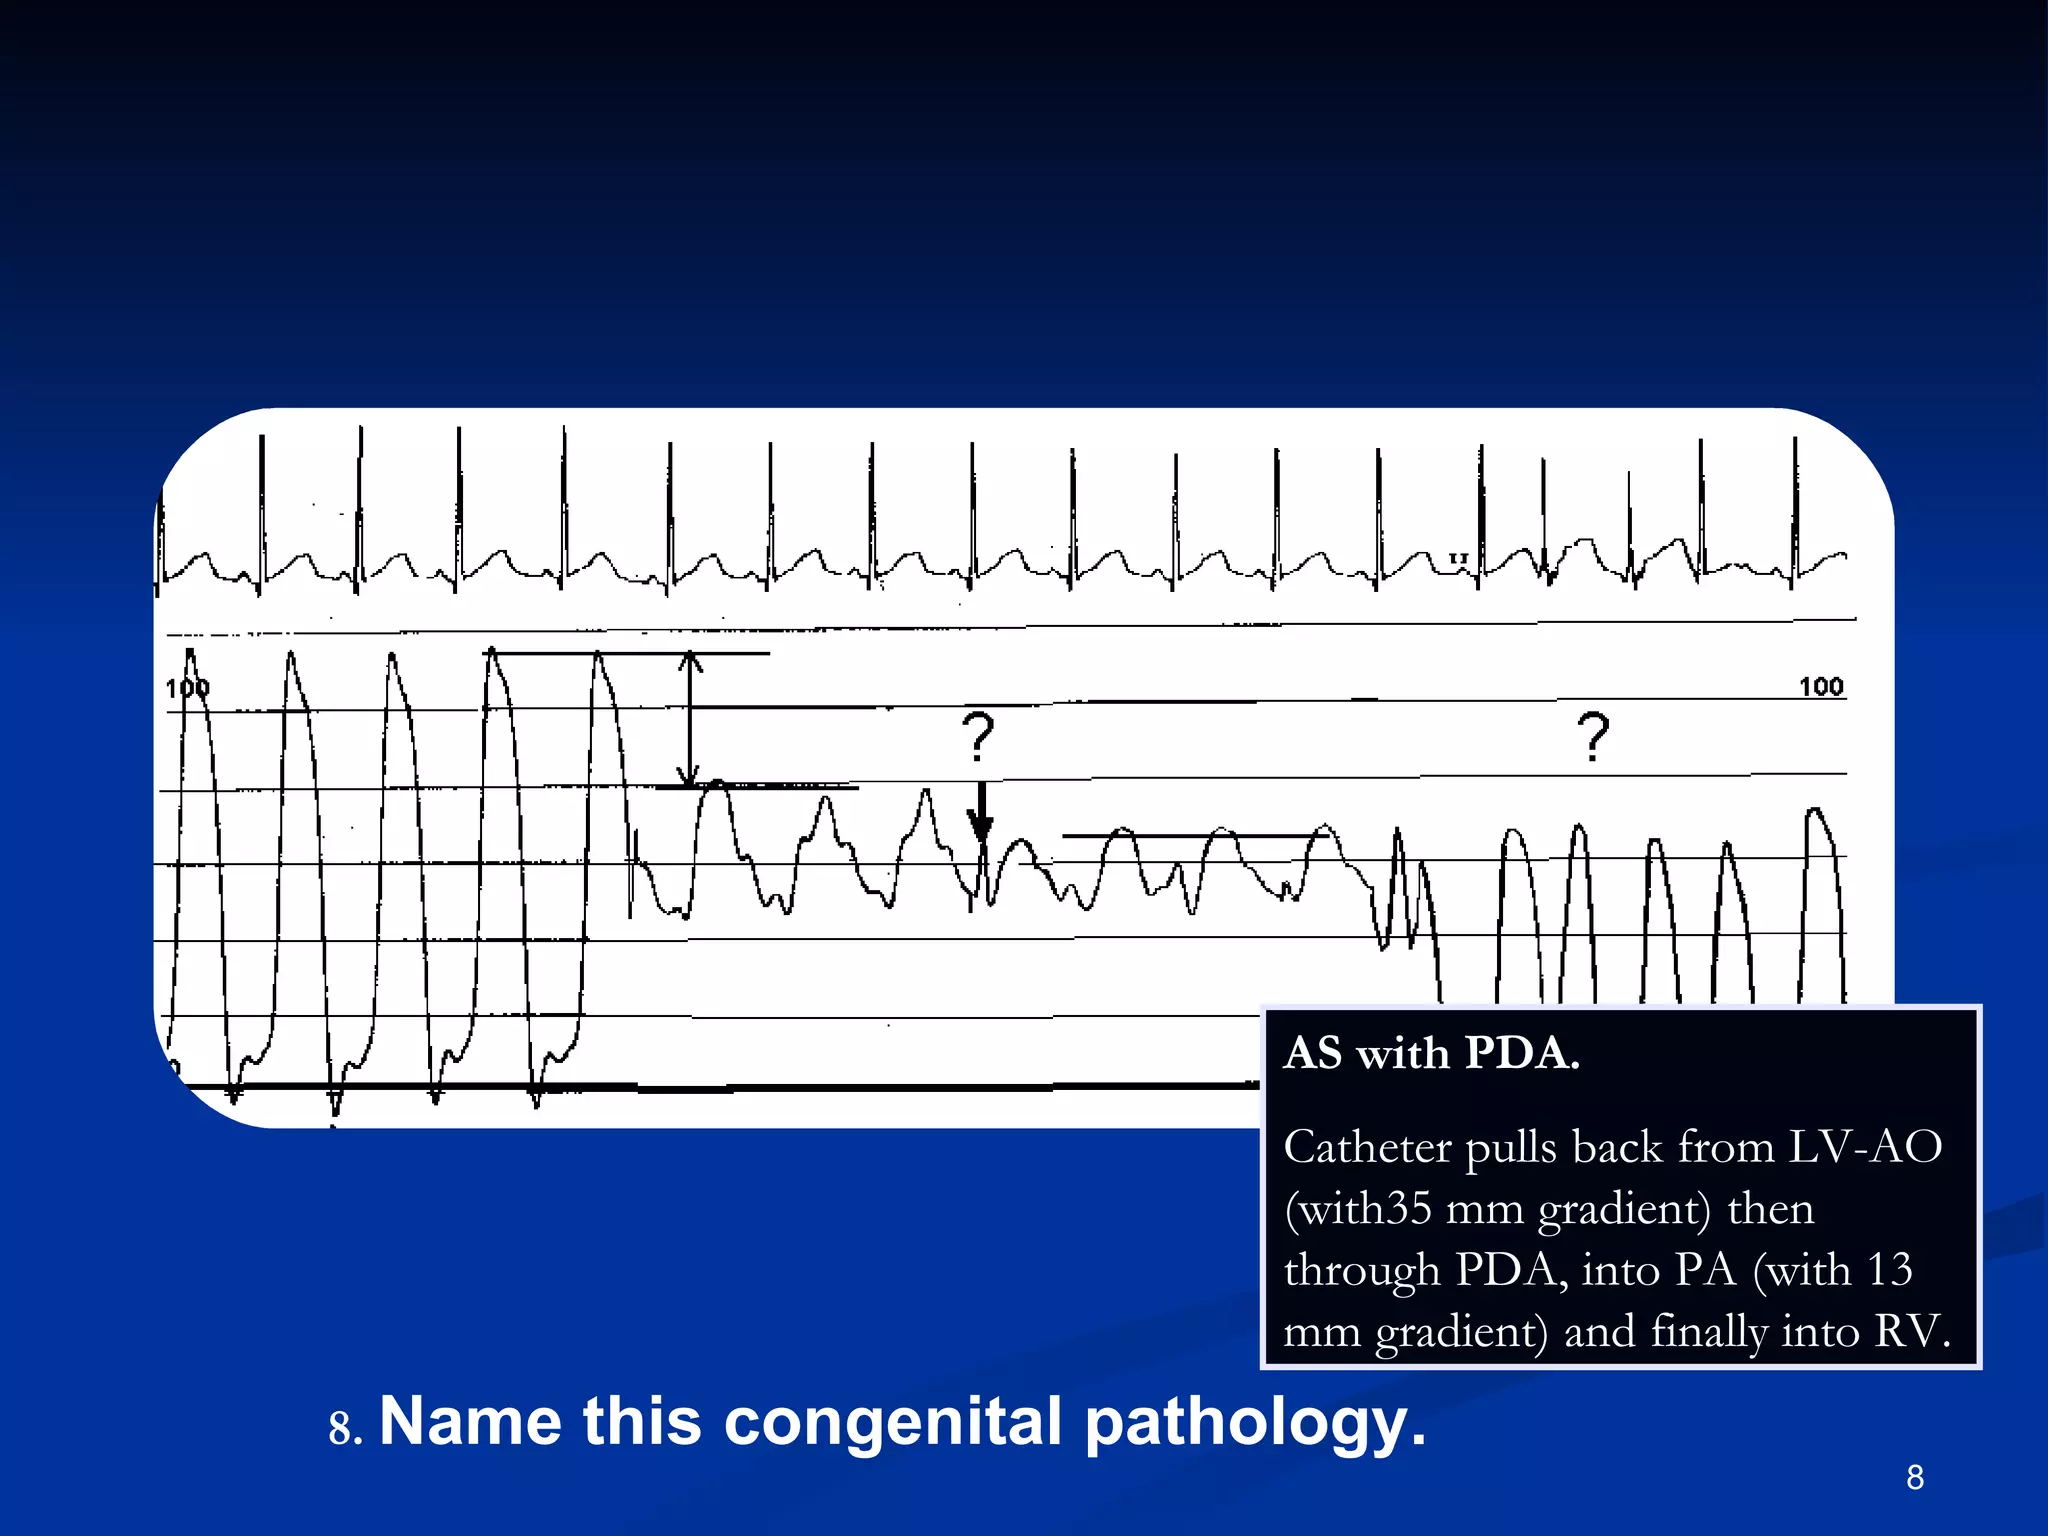

.   Name this congenital pathology. AS with PDA.  Catheter pulls back from LV-AO (with35 mm gradient) then through PDA, into PA (with 13 mm gradient) and finally into RV.